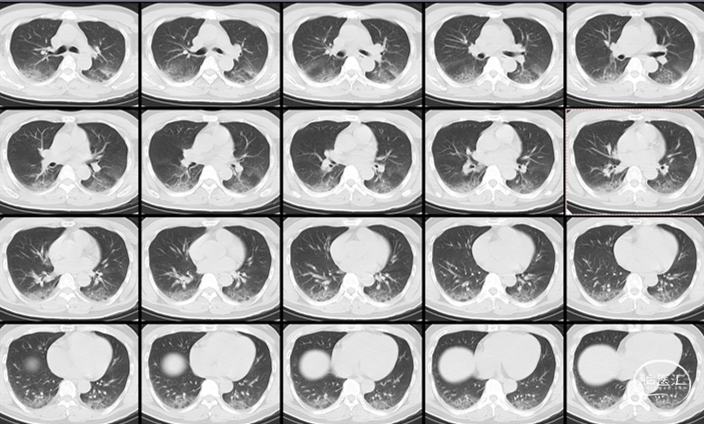

肺CT:

双肺多发炎性改变,符合吸入性肺炎表现。

术后检查:次日CT

术后4天,肺部CT显示吸入性肺炎明显好转

术后14天,头颅CT示蛛网膜下腔出血完全吸收,头痛缓解,痊愈出院。